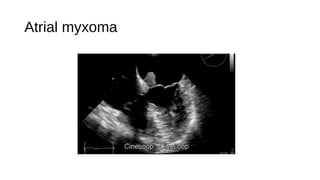

Atrial myxoma